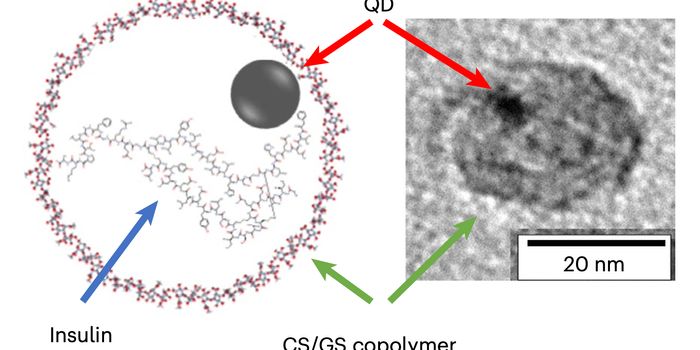

JUL 09, 2024Drug Discovery & DevelopmentA nanoparticle delivery system shows promise for aiding the recovery surgically-repaired tendons.